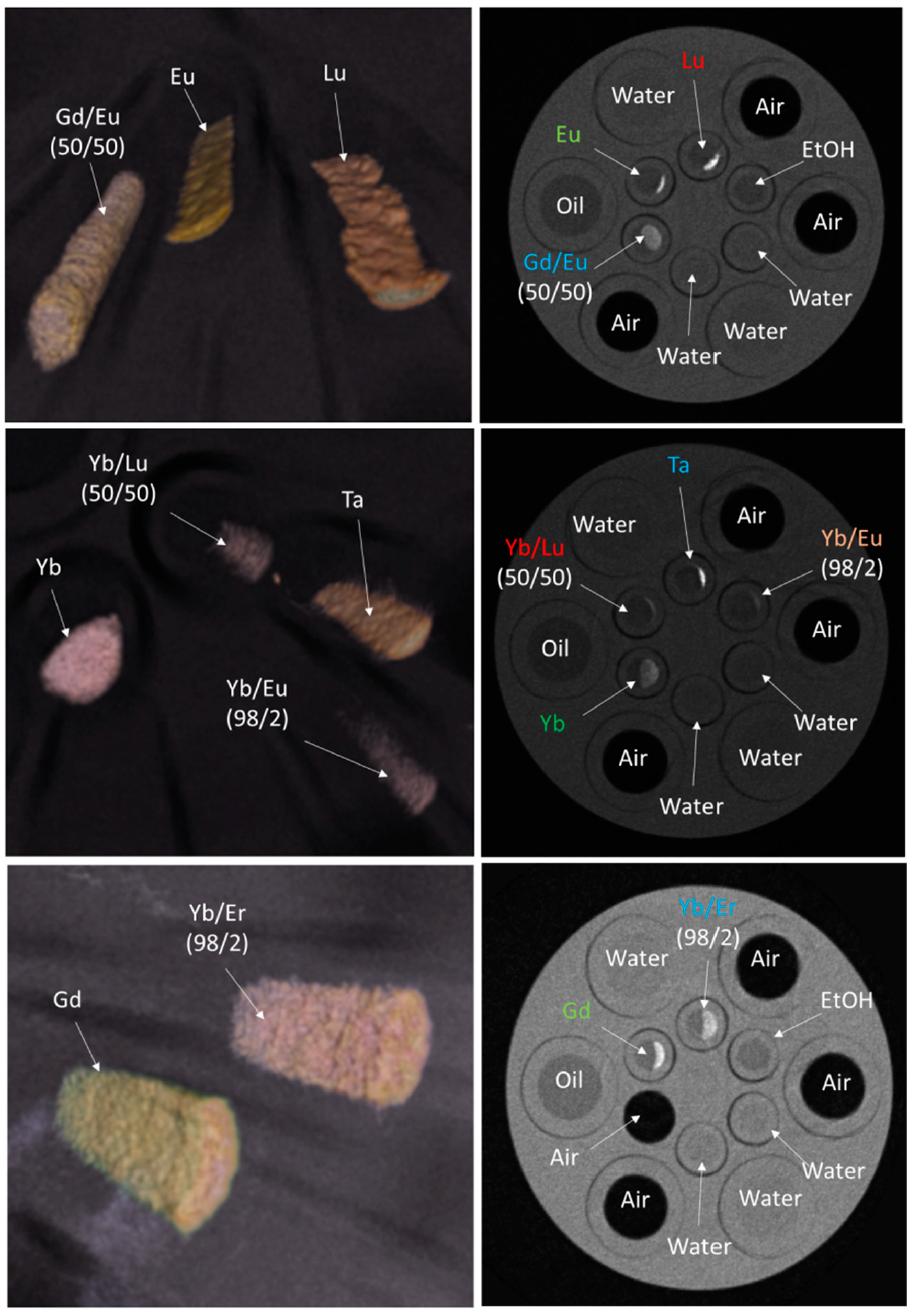

- Contrast agent development for spectral X-ray imaging (in collaboration with the Biomarker Development Laboratory, UMass Chan Medical School)